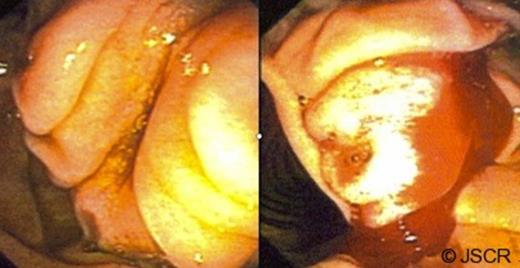

A 66 year-old woman was referred to the surgeon’s office when she presented with a five month history of upper abdominal pain and diarrhoea. A CT scan of the abdomen and pelvis obtained upon presentation to the emergency department showed intrahepatic and extrahepatic bile duct dilatation. There were no masses in the cystic bile duct (CBD) or the pancreas. This was followed by an oesphago-gastro-duodenoscopy (OGD) that showed a prominent ampulla (Figure 1) with very hard tissue suspicious for malignancy. On oesophageal ultrasound, there was a submucosal mass, isoechoic, not invading the muscularis propria (Figure 2), and without involvement of the pancreas. There were no enlarged lymph nodes. The biopsy specimen was positive for a focal carcinoid tumor on a background of duodenitis. The cells stained positive for Chromogranin, Synaptophysin and Cytokeratin.